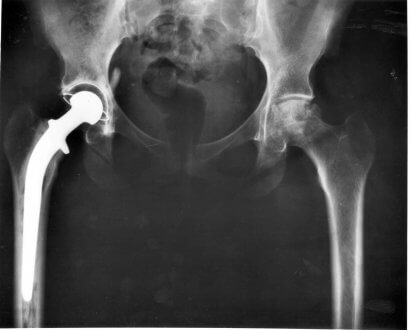

- Substituição total do quadril. Substitui-se a articulação natural por um molde elaborado com materiais sintéticos.